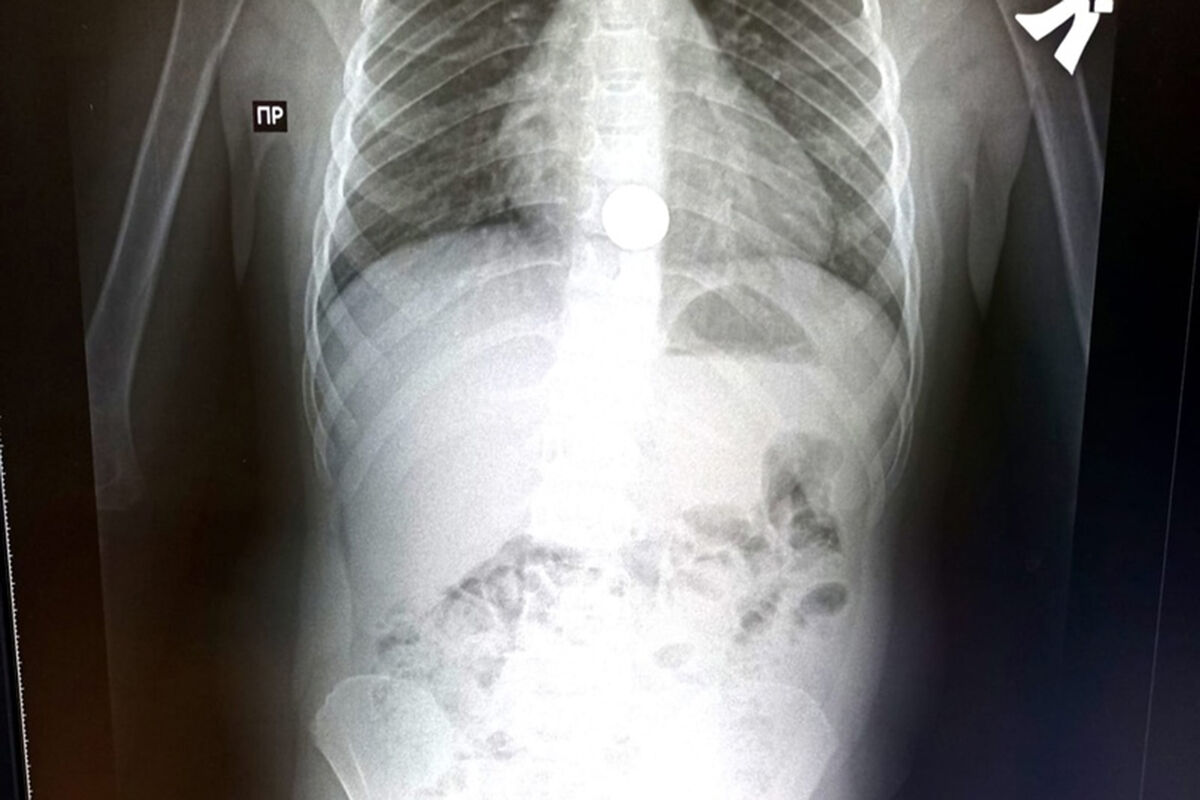

Врачи детской больницы Салавата помогли пятилетнему мальчику, который случайно проглотил монету. Об этом сообщил главный врач медицинского учреждения Алик Янышев.

В приемный покой детской больницы обратились родители с пятилетним мальчиком, они сообщили, что сын играл в комнате и случайно проглотил монету. В ходе обследования инородный предмет был обнаружен в пищеводе ребенка.

Монету удалось извлечь с помощью эндоскопических инструментов под общим наркозом. Состояние мальчика не вызывает у медиков опасений, спустя сутки он был выписан домой.